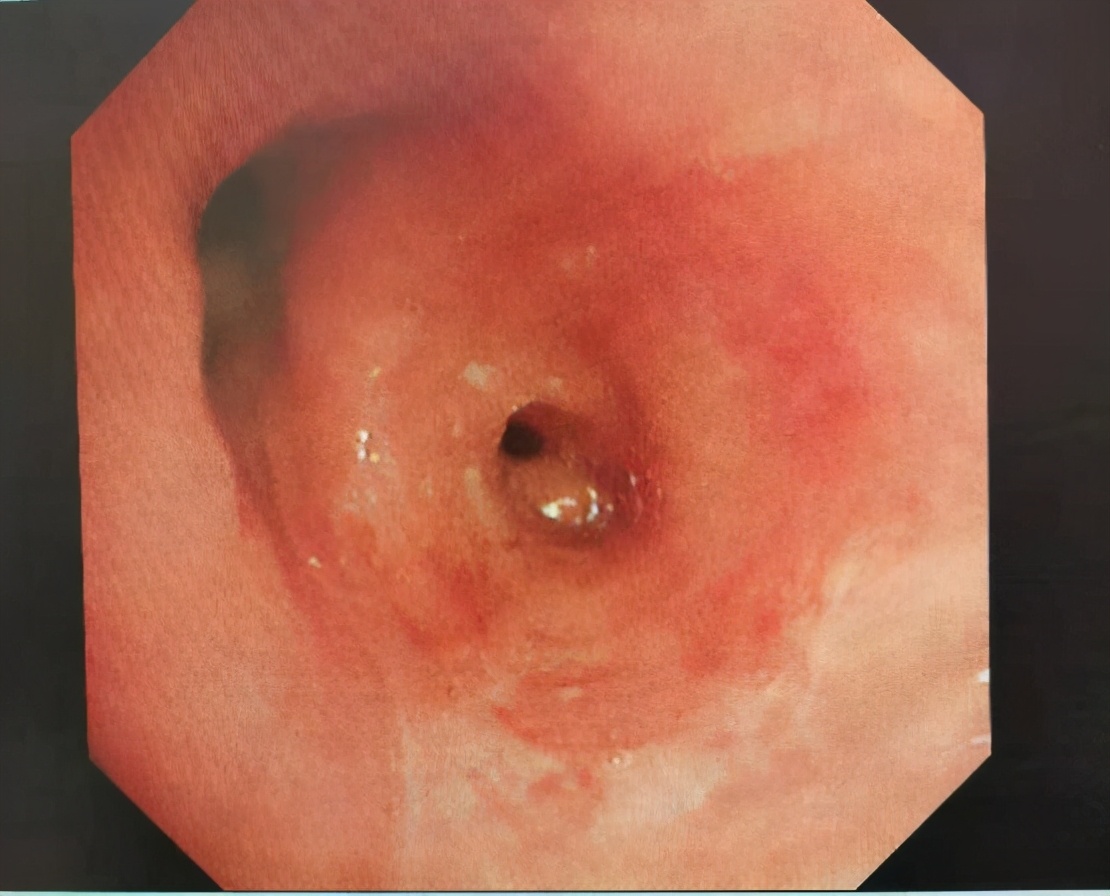

支气管腔内肿物冻融后,左舌叶通畅

入院给予积极胸腔穿刺引流后,安福成主任给予患者行支气管镜检查可见左舌叶支气管开口处巨大腔内肿物,阻塞左舌叶约95%,这正是造成患者呼吸困难的主要原因。

经过支气管镜活检,病理诊断为真菌感染,之后给予两次支气管镜下两性霉素B药物滴入治疗,并给予全身抗真菌治疗,咳嗽、咳痰、胸闷症状有所改善,考虑支气管内肉芽肿阻塞远端气道导致病情的反复发生,与患者家属充分沟通后,予精心准备,在麻醉医生的配合下,完成了经支气管镜二氧化碳冻融,经多次镜下治疗,患者左舌叶气道基本通畅。